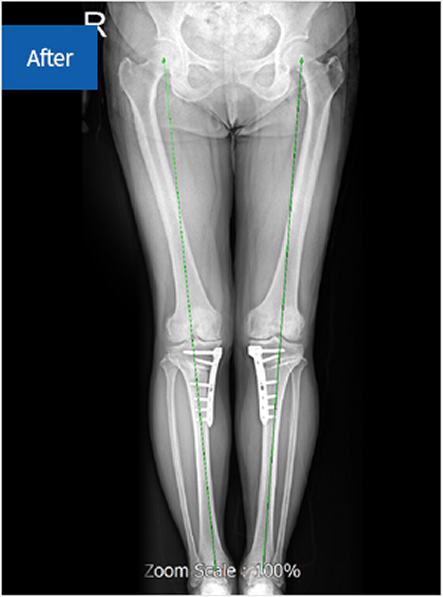

좌식 생활이 많은 우리나라에서는 무릎 관절염 환자에게 O자형 변형이 자주 나타나는데,

이는 무릎 관절을 이루는 연골, 뼈, 인대 등이 특히 내측에서 손상되기 때문입니다.

이러한 내반변형이 한 번 발생하면 이후 지속적으로 악화되어 내측에 집중된 변형이 진행됩니다.

절골술을 시행하여 휜 다리를 교정, 정상 각도를 유지

before img after img